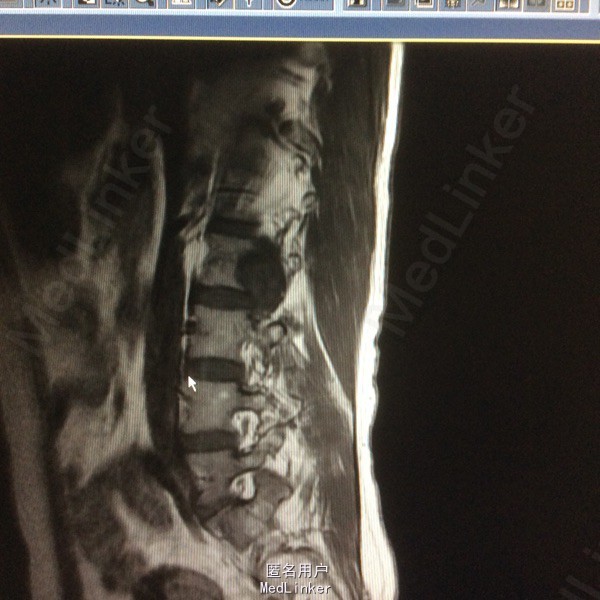

患者双下肢无明显浅感觉减退,肌力V级,肌张力不高,二便控制满意,病理征阴性。 腰椎核磁:腰1-4椎体右侧右肾下方团块状占位,大小约8#⃣6.8Cm,等T1长T2信号 腰椎Ct:占位周围见弧形钙化灶

腰椎神经鞘瘤 切除右侧横突,见腰2神经根延伸呈膜状,沿腰2神经跟出口将神经切断,完整取出肿物。